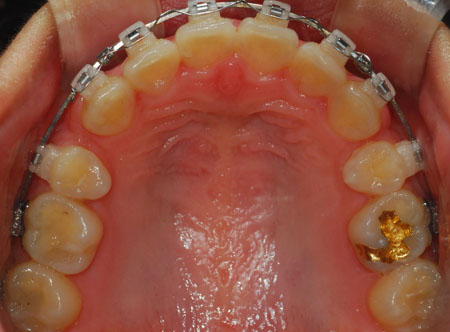

상악 사진

저기 동그라미 친 부분이 남은 발치 공간 입니다. 많이 줄어들엇죠?

노란 동그라미는 남은 발치 공간 입니다.

예전에 처음 교정 할 때 이가 전체적으로 앞으로 나와서

뒤에 이들이 앞으로 쏠려 있어서 공간이 있다고 했었는데요.

지금 파란 동그라미 보시면 그 공간이 거의 없습니다. 음하하하하하하핳